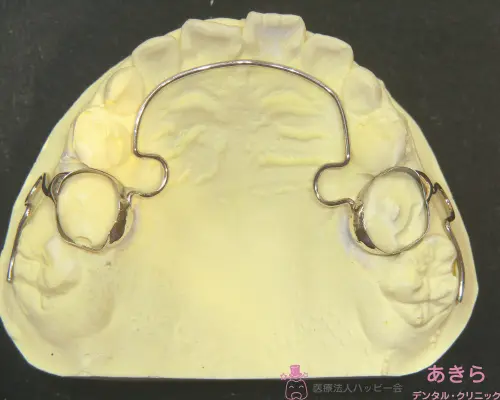

バンド装着⇒型取り

型

リンガルアーチ(6歳臼歯を中へ入れる)セット